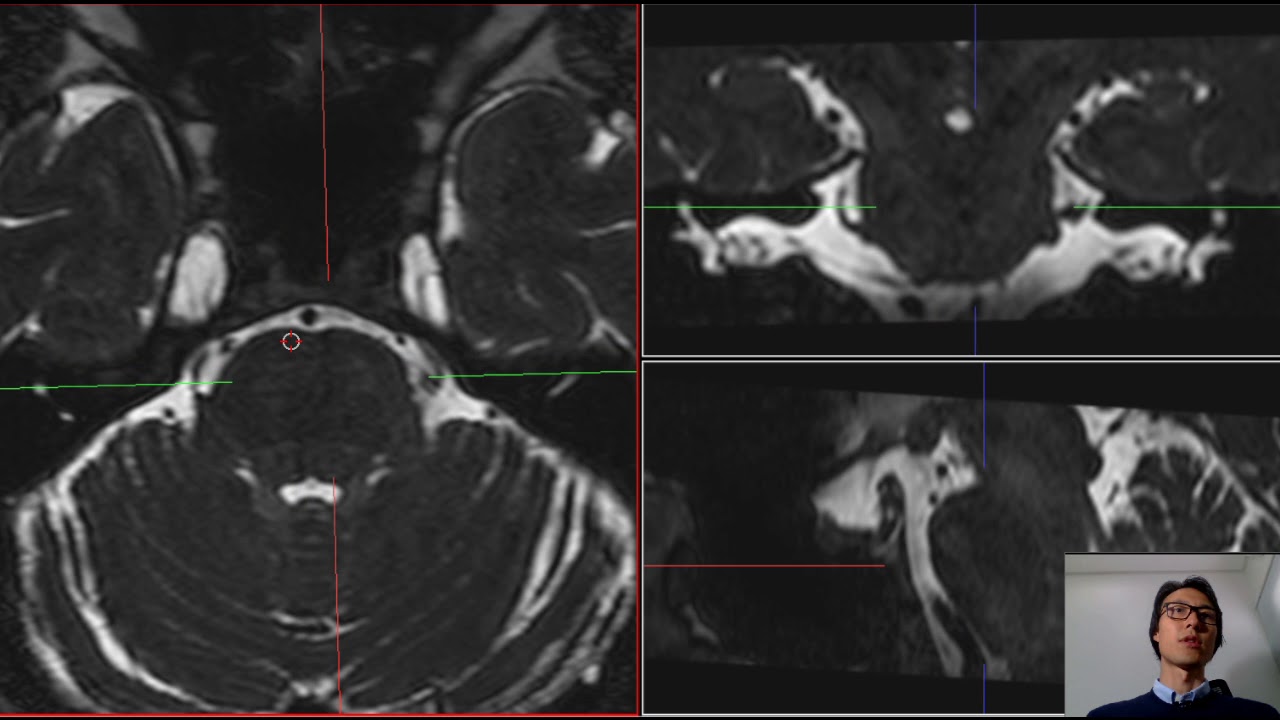

vem e tem mais uma alternativa que a gente vai ver aqui vamos ver a próxima alternativa para lidar com essa dor a outra alternativa é a compressão por balão então da mesma forma é colocada a agulha só que ao invés de colocarmos um eletrodo aqui por dentro é colocado um cateter que tem um balãozinho aqui na ponta nós insufl amos esse balão por um determinado tempo específico essa insuflação comprime o nervo trigêmeo e causa uma falta de sangue temporária no eu perto de irrigação perde irrigação o tempo ter uma imagem real nesse procedimento para a

gente dar uma olhada aqui para entender um pouco melhor para ver então aqui tá mostrando agulha e aqui o balão sendo insuflável a gente vê isso com o raio x específico do centro cirúrgico quando perde sangue perde irrigação nessa região para de doer parou de doer em mais de noventa e cinco porcento dos carros imediatamente idiota não só deve ser uma livremente a maioria dos pacientes chegam chorar é um livro bastante importante de ar livre e depois de alívio uma dor muito conhecida e a dor oncológica dor do Câncer essa dor ela é devidamente tratada